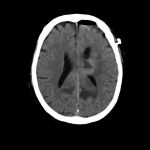

症例 '15年4月

No.

※ 画像をクリックすると拡大表示します。症例No.は平成29年から起算しています。

年_番号

手術年月

患者年齢

’15_48

'15年4月

60代

病名

術式

備考

脳腫瘍

断層撮影

手術前

1

手術前2

手術後